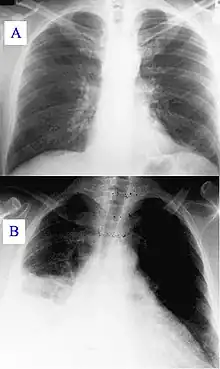

Signes radiologiques

Pneumopathie atypique